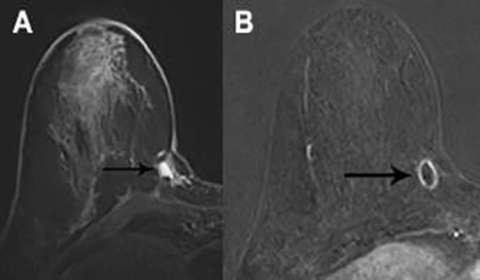

Fat necrosis has a variable imaging appearance, with many cases requiring follow-up imaging (BI-RADS 3) or biopsy (BI-RADS 4).2 Internal fat signal intensity is a classic imaging feature (Figure 3a). Enhancement is variable and may be rim, focal, or diffuse (Figure 3b).3 Calcifications may be seen as signal voids. Correlation with mammography is helpful in identifying central fat density as well as the typical calcifications seen in fat necrosis.

FIGURE 3A: T1-weighted image without fat saturation. Status-post lumpectomy with fat signal intensity within the surgical scar. FIGURE 3B: T1-weighted post contrast image with fat saturation. Enhancement at the margins of presumed fat necrosis. This enhancement was followed and remained stable.